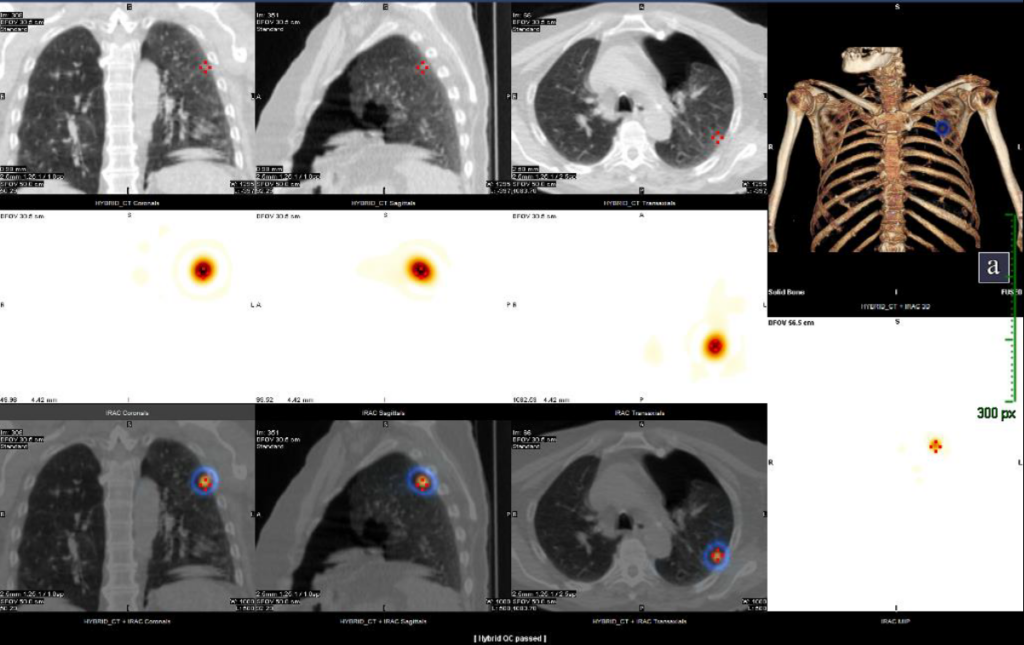

CASO 2: Hombre de 70 años. En TC torácico de enero de 2024 se observa una opacidad en vidrio deslustrado en LSI, sugestiva de adenocarcinoma. La lesión no muestra hipermetabolismo en [18F]-FDG, tampoco en otras localizaciones.

Imágenes TC (fila superior), SPECT (fila central) y SPECT/TC (fila inferior), y reconstrucción 3D del TC en ventana hueso fusionada con el SPECT (arriba derecha).

Imagen tomada con gammacámara portátil de la pieza quirúrgica de segmentectomía amplia.

En este segundo caso, la AP es de lesión probablemente premaligna, con márgenes libres a la línea de grapas de 1,5 cm.